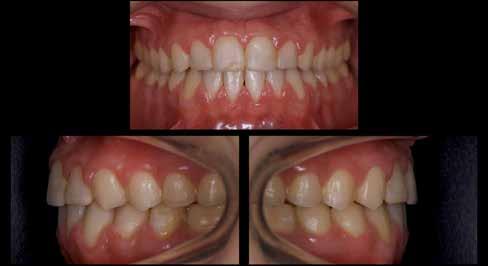

A páciens a megkezdett kezelések folytatása miatt 2017ben ismét felkereste a rendelőnket (7. ábra). Ekkor egy új intraorális lenyomatvétel történt (Carestream 3600).

A már előzetesen preparált felső frontfogak csiszolt csonkjainak megtartottuk az eredeti formáját. Az alsó és felső őrlőfogak preparációja nem volt szükséges (1.7-1.4, 2.4-2.7, 3.7-3.4, 4.4-4.7), az alsó kismetsző fogakat minimál invazív módon készítettük elő. Az előkészítést követően új digitális lenyomat készült. Az így kapott digitális adatokat továbbítottuk a fogtechnikai laboratóriumba (9. ábra). A virtuális modellt ezek alapján hozták létre (AnatomicLab), és a minta elkészítéséhez szükséges STL fájlt továbbították egy háromdimenziós nyomtatóra (SolFlex 650, VOCO), amely segítségével elkészítették az új mintát (V-Print model, VOCO).

A végső restaurátumokat (héjakat és koronákat) Ce-

ramill Mind tervező program segítségével (AmannGirrbach) digitálisan megtervezték, majd frézgép segítségével (CeramillMotion 2, AmannGirrbach) li thium-diszilikát tömbökből (VITABLOCS TriLuxe forte for CeramillMotion 2, AmannGirrbach) kifaragták (10. ábra). Miután a fogpróba során ellenőrizték és megfelelőnek találták a pótlások széli záródásának a pontosságát, valamint az elkészült restaurátumok esztétikai megjelenését, ezután egy ajak- és szájterpesz került felhelyezésre (OptraGate, IvoclarVivadent).

A koronákat (1.3-1.1 és 2.1-2.3) és a héjakat (1.7-1.4, 2.4–2.7, 3.7-3.1, 4.1–4.7) fényrekötő adhezív rendszerrel rögzítették a pillérfogakhoz (Futurabond U ésBifix QM, VOCO). A polimerizációhoz egy nagy teljesítményű LED polimerizációs lámpát használtak (Celalux 3, VOCO), (1112. ábrák).

A kifolyó ragasztóanyagot ezt követően eltávolították, majd az okklúziót a T-Scantechnológia (Tekscan) segítségével ellenőrizték, majd a szükséges mértékben korrigálták. A véglegesen rögzített kerámiapótlás védelme érdekében a páciensnek a továbbiakban egy kivehető, átlátszó műanyag fogvédő sínt kellett viselnie. A pótlásokat 6 hónap múlva ellenőrizték. Az át adott fogpótlások stabilan rögzültek, és nem találtunk sérülésekre, repedésekre utaló jeleket (13-15. ábrák). A páciens arról is beszámolt, hogy a harapás megemelése óta megszűntek az őt rendszeresen gyötrő fejfájásai.